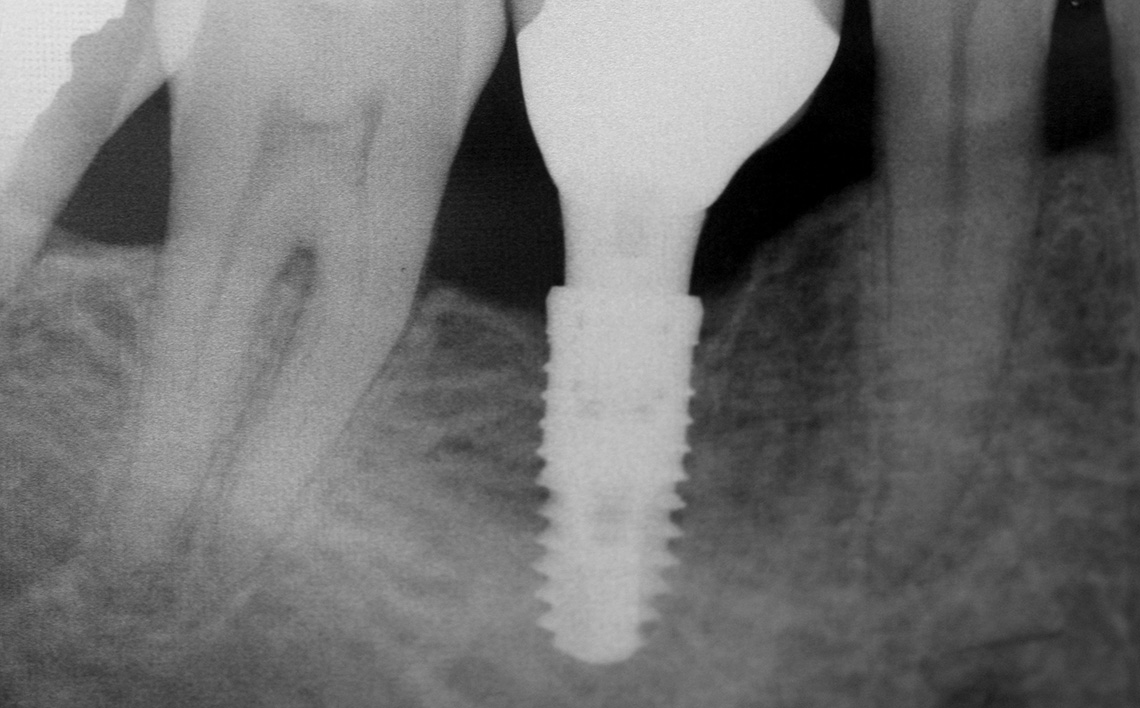

Tratamentul efectuat cu instrumente specifice, sub anestezie, presupune indepartarea pulpei si a nervului, curatirea canalelor dentare si obturarea lor in final.Tratamentul mecanic al canalelor (largirea lor) se efectueaza prin penetrare cu ace din nichel-titan. Canalele curatate se obtureaza prin aplicarea de gutaperca. Materialul folosit pentru obturare este bioinert, neiritant si neresorbabil.

In situatii speciale, daca pe aceasta cale nu se obtine vindecarea intrucat infectia s-a infiltrat adanc in radacina dintelui, este necesara si efectuarea unei rezectii apicale (extirparea microchirurgicala a varfului infectat al radacinii dintelui).

Rezectia apicala se efecturaza pe scaunul stomatologic, sun anestezie locala sau chiar generala in cazul unor pacienti mai sensibili. Dupa descoperirea tablei osoase se efectueaza trepanarea osoasa cu indepartarea tesutului osos afectat si a apexului dentar. In mod curent se procedeaza la sigilarea zonei. In anumite cazuri, este necesara completarea cu os sintetic. Suturarea plagii se efectueaza cu fir neresorbabil care va fi indepartat ulterior. Pentru a preintampina aparitia de omplicatii septice se aplica tratament antibiotic.